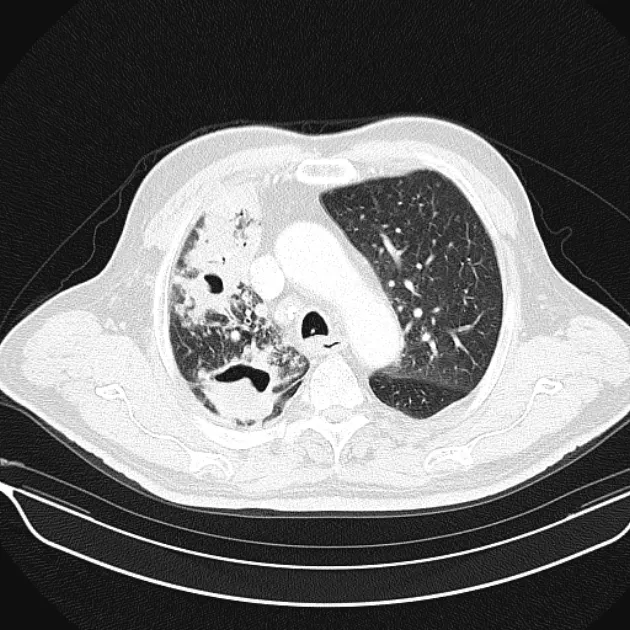

Post-primary pulmonary tuberculosis

대부분의 환자는 다음 두 곳에 생김

Posterior segments of the upper lobe

superior segments of the lower lobe

Typical findnigs

1) Patcy consolidation 또는 poorly defined linear and nodular opacities

2) air-fluid level : airway와 communication 형성 의미